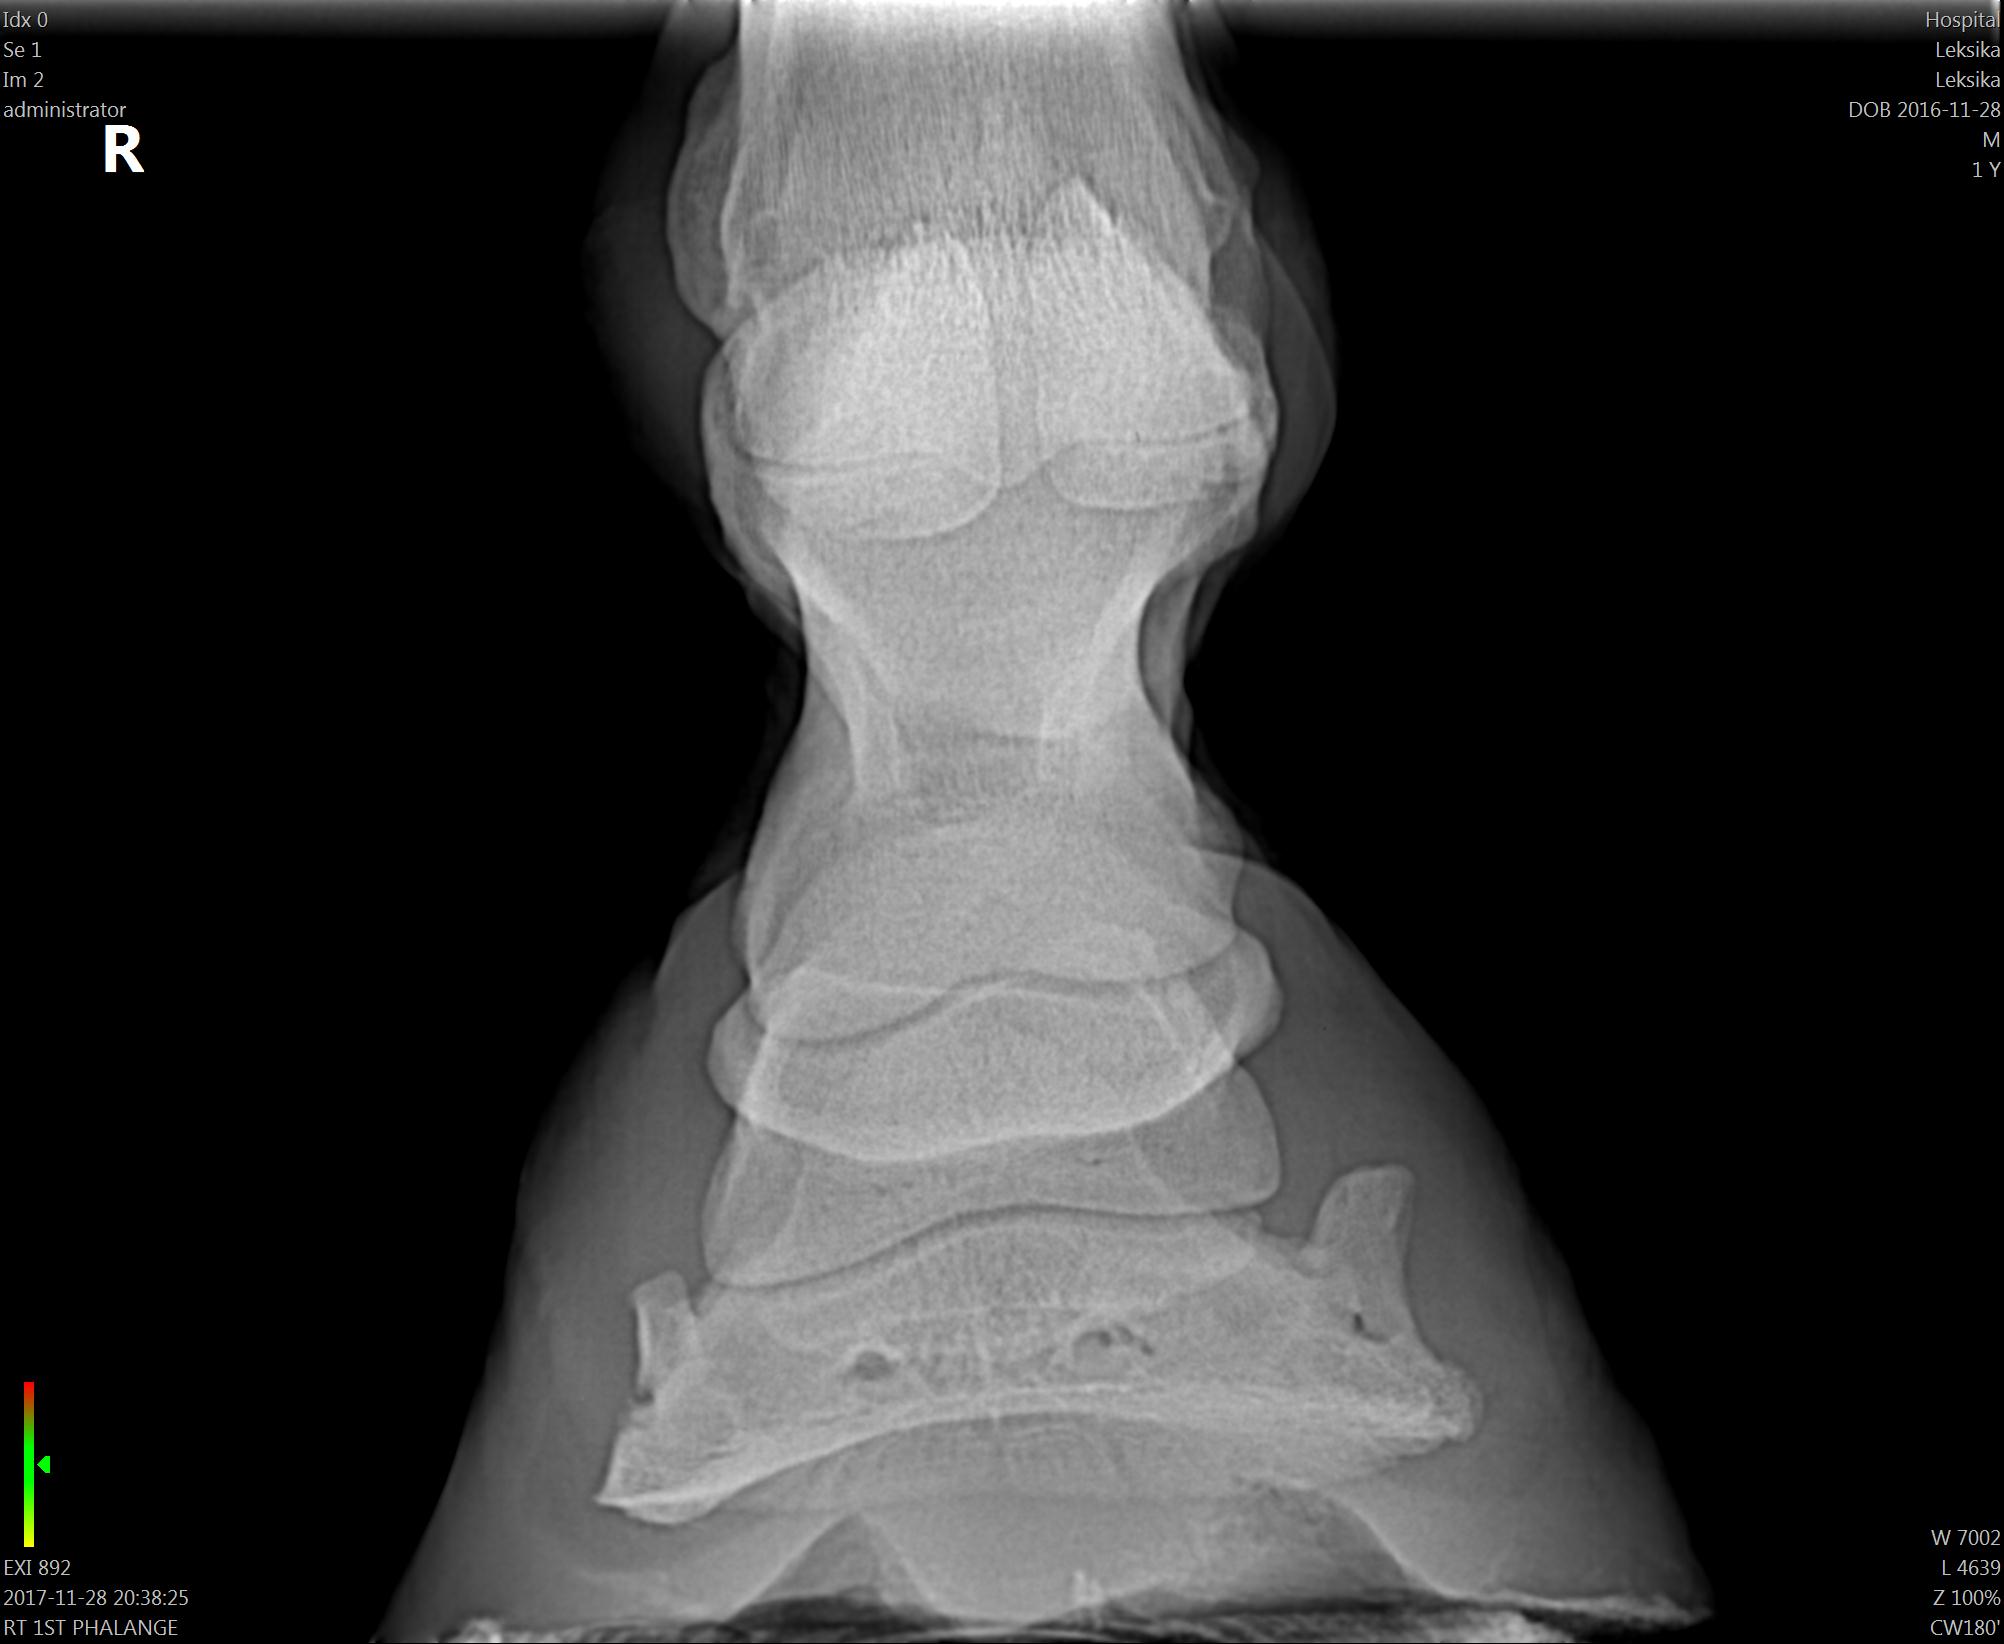

О! Мы же ещё лапу любимую свою зарентгенила.

Моя раскривушечка:)